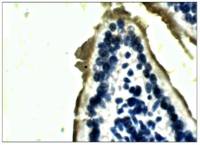

IHC-P analysis of human colon, ulcerative colitis tissue using GTX75391 CD16 antibody [2H7]. Note intense membrane staining of infiltrating natural killer cells, granulocytes and activated macrophages.